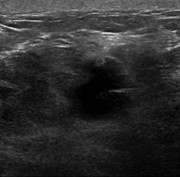

Laparoscopic drainage of abdominal wall abscess from spilled stones post-cholecystectomy

Vincent Chong and Rishi Ram

Journal of Surgical Case Reports, Volume 2015, Issue 7, July 2015, rjv077, https://doi.org/10.1093/jscr/rjv077